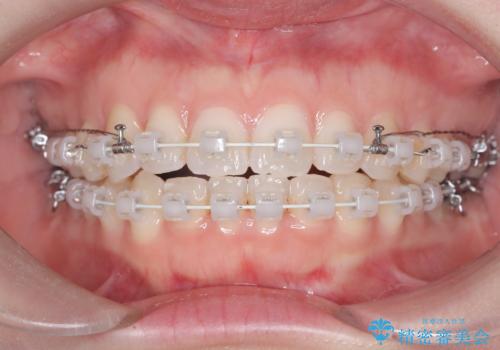

- 20代女性

- 右上の八重歯と歯並びのデコボコを気にされて来院されました。精密な検査の結果、歯列のスペースがわずかに不足していることが判明。患者様の「抜歯を避けたい」というご希望を最大限に尊重し、アンカースクリュー(TAD)を用いて奥歯(臼歯部)全体を後方へ移動させることで、八重歯が並ぶスペースを確保する治療計画を立案しました。装置にはワイヤー矯正を使用し、確実で効率的な歯の移動を目指します。

今回のワイヤー矯正治療では、抜歯せずに歯を並べるスペースを作るため、特殊な小さなインプラントであるアンカースクリュー(TAD)を一時的に使用しました。このアンカースクリューを固定源として、奥歯(臼歯部)全体を後方へ遠心移動させました。従来の矯正では難しかったこの奥歯の移動を確実に行うことで、前歯の八重歯を適切な位置に並べるスペースを確保。治療の結果、抜歯することなく右上の八重歯と叢生が解消され、機能的にも審美的にも整った美しい歯並びを獲得していただけました。